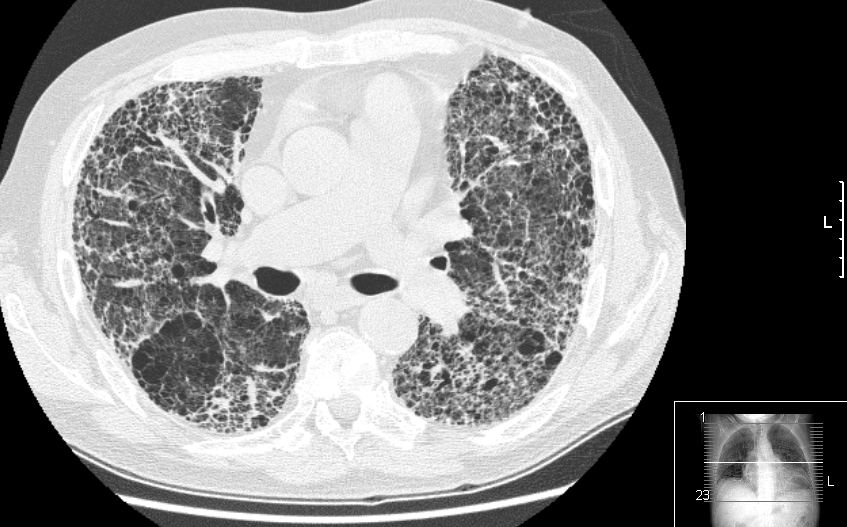

Eficacia del rastreo de cáncer de pulmón en poblaciones seleccionadas

Los resultados del estudio británico UKLS muestran reducción de la mortalidad por cáncer de pulmón a partir del rastreo en pacientes de alto riesgo con una única tomografía computada de baja dosis. Un metaanálisis de nueve ensayos aleatorios proporciona un apoyo inequívoco para la detección del cáncer de pulmón en grupos de riesgo identificados. The Lancet Regional Health Europe, 11 de septiembre de 2021.